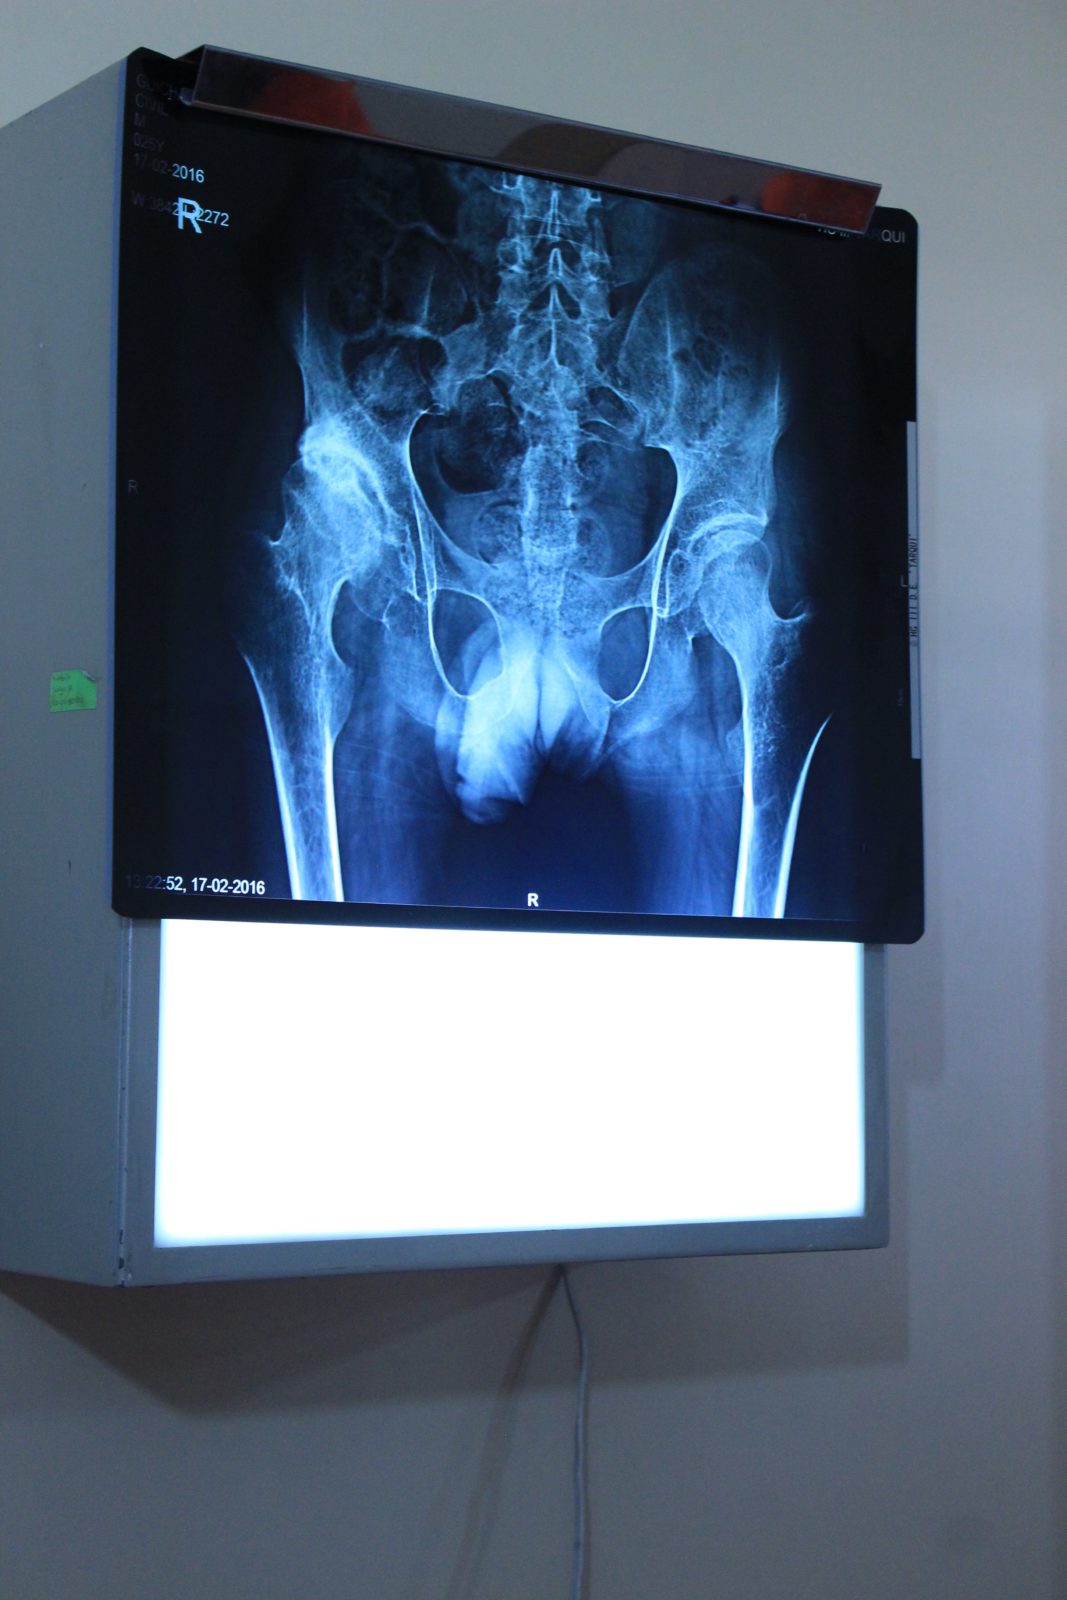

That process was put into motion at the clinic where TNMS’s doctors, nurses, physiotherapists, joint replacement specialists and general volunteers evaluated over 40 patients to assess viability for surgery this week. When we arrived today at the clinic, most of these patients were waiting outside, and were very happy to see our team (just as we were happy to see them!). Every team member worked especially hard today as we funnelled each patient, one by one, in to see the doctors. Those team members able to translate were in high demand all day, and did incredible work today as they were pulled in several directions by doctors, nurses and volunteers needing to communicate with our patients. The experience was inspiring and, at the same time, deflating, as we all felt the excitement for those who were to receive promising life changing surgery and disappointment for those who were not candidates for surgical help (for various medical reasons). All went smoothly and 28 patients were booked for surgery (3 on the waiting list in case of cancellations).